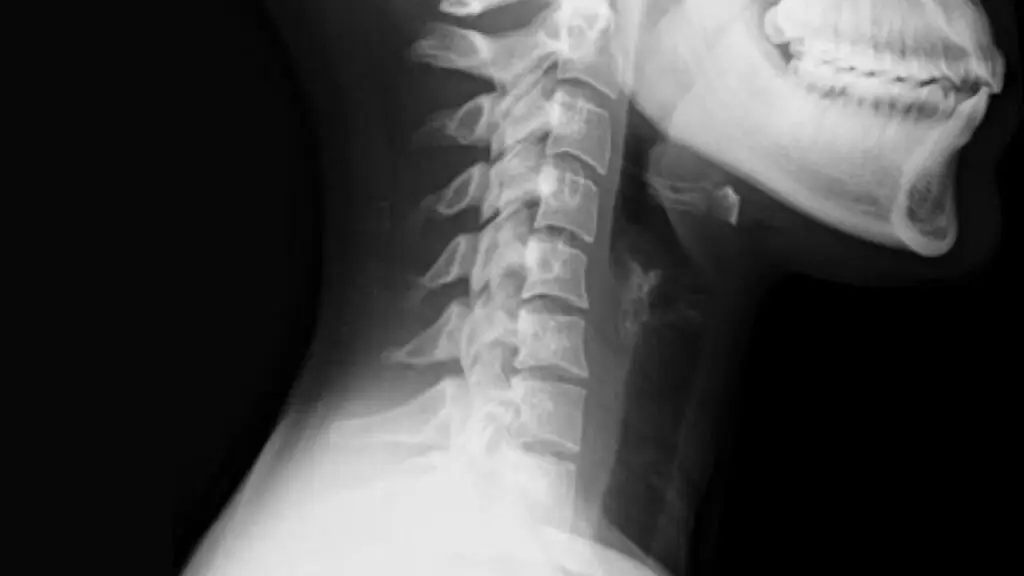

One of the challenges with whiplash is that the injury is often invisible due to the nature of the injury, which are often internal and involve the soft tissues of the neck. X-ray reports often state no abnormalities can be found as they do not reveal soft tissue injuries which may be frustrating. However, as X-rays do not provide information regarding pain levels, they are primarily utilized to clear any sinister bone injuries and this in itself is good.